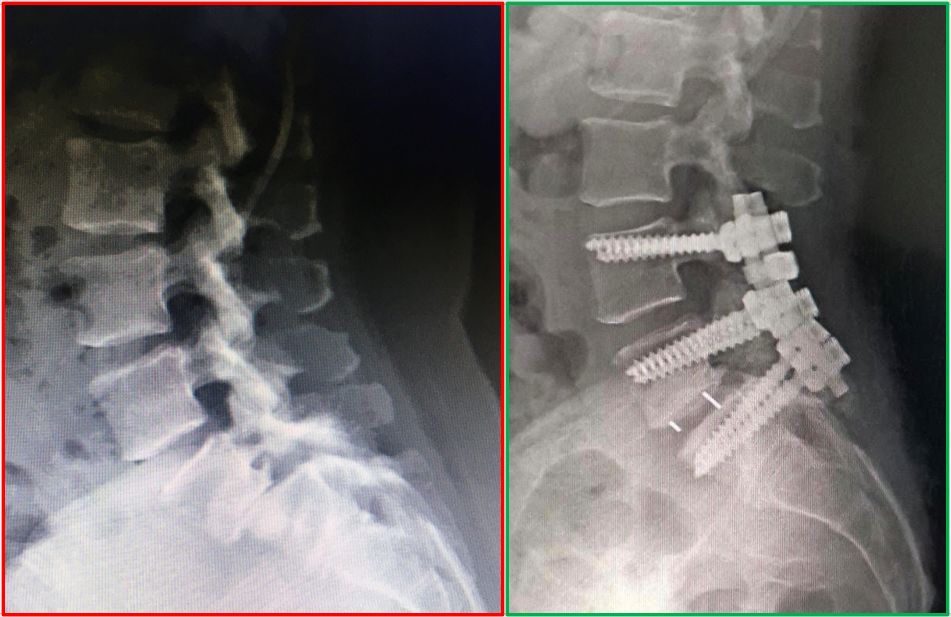

La atención personalizada para cada uno de los pacientes, además de las herramientas diagnósticas mas sofisticadas, son el estándar de excelencia con el que trabajamos para ofrecer la mejor solución a su problema de columna. Así sea un decisión conservadora o quirúrgica, cada uno de los tratamientos se realiza a la medida de cada paciente, para mejorar su calidad de vida.

• Cirugía de columna

• Artrodesis cervical anterior

Tengo tiempo que me atiendo con el Dr, Chapa, quie me hizo una Cirugía de Columna Cervical, todo ha sido excelente desde antes de la Cirugia, durante y el seguimiento

Excelente Médico, mas que recomendado, la cirugía de columna de mi mama fue todo un éxito, Gracias a su excelente trabajo Gracias por todo Doctor